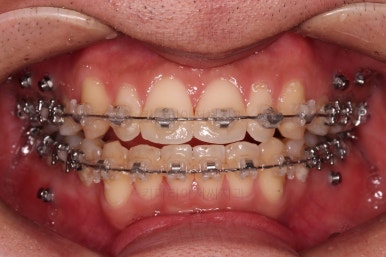

치료시작 6개월 정도 시점의 모습인데, 이정도만 해도 교정이 잘 된 듯 하지만 이제 시작입니다.

얼굴 모습 개선을 위해 해야 될 점들이 많습니다.

교합이나 가지런한 느낌 매우 좋아졌고요.

특히 옆 라인에서도 둥글었던 윗입술도 오목한 곡선이 생기면서 돌출감이 좋아졌고 턱끝의 윤곽도 생기면서 무턱 느낌도 좋아졌습니다.

윗니의 위치를 보면 처음은 아랫입술에 가려질 정도로 아래로 내려와 있었는데 치료 후에는 앞니가 보이는 정도로 위치 조절이 잘 되었네요.